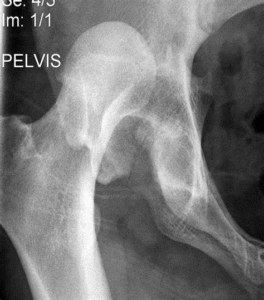

خلع مفصل الورك

كسور عنق الفخذ

الأشعة السينية (AP، ومناظير Judet) قد تكون الخطوة الأولى.

إلا أن التصوير المقطعي CT هو المعيار الذهبي للتشخيص، إذ يحدد نمط الكسر وامتداده بدقة ويُستخدم لتخطيط العلاج الجراحي.

أي خلع للمفصل يجب رده بشكل عاجل لتجنب أذية غضروفية إضافية.